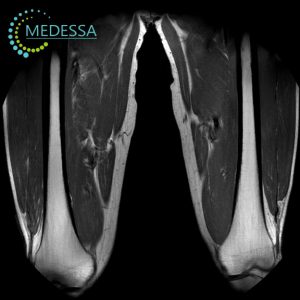

Магнітно-резонансна томографія (МРТ) суглобів та м’яких тканин — це високоточний метод медичної діагностики, який дозволяє детально візуалізувати анатомічні структури опорно-рухового апарату без використання іонізуючого випромінювання. Дослідження дає змогу оцінити стан колінного, плечового, тазостегнового, гомілковостопного, ліктьового, променево-зап’ясткового та інших суглобів, а також м’язів, сухожиль, зв’язок, менісків, фасцій та навколосуглобових тканин.

МРТ 3.0 Тесла в Одесі забезпечує максимальну деталізацію структур суглоба, що особливо важливо для раннього виявлення пошкоджень зв’язкового апарату, хрящової тканини та внутрішньосуглобових елементів. Високопольний томограф дозволяє діагностувати патології на ранніх стадіях, коли клінічні прояви можуть бути мінімальними.

Які структури візуалізує МРТ суглобів

- м’язи;

- навколосуглобові м’які тканини.

Які патології виявляє МРТ суглобів та м’яких тканин

- спортивні травми;

- пошкодження м’язів;

- часткові та повні розриви сухожиль;